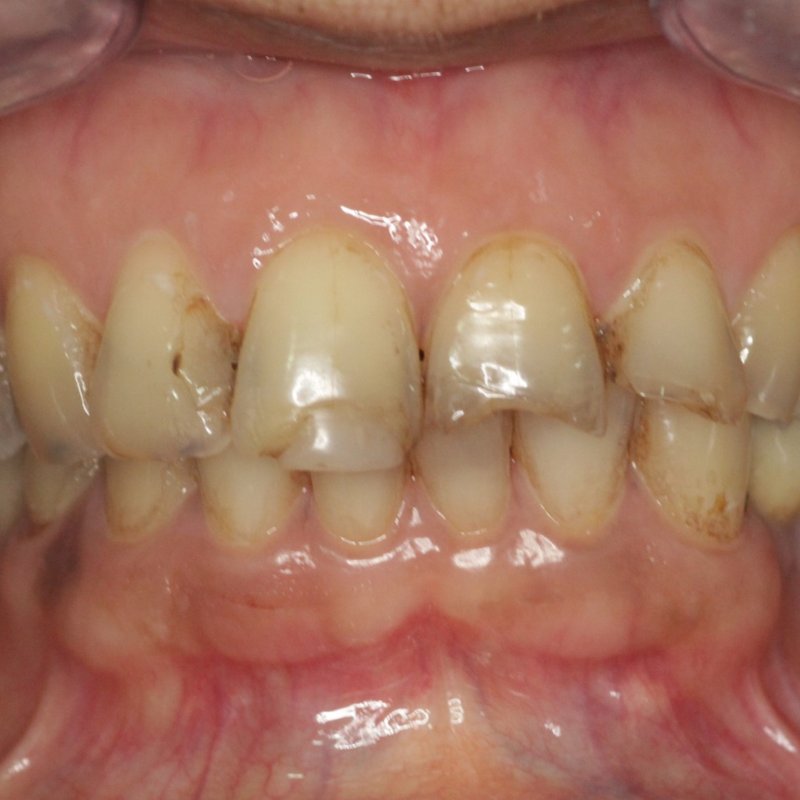

Before composite work

Before After

Composite Restoration

Tooth-coloured fillings

Worn edges and discolouration restored with bonded composite — same-day, conservative, and perfectly shade-matched.